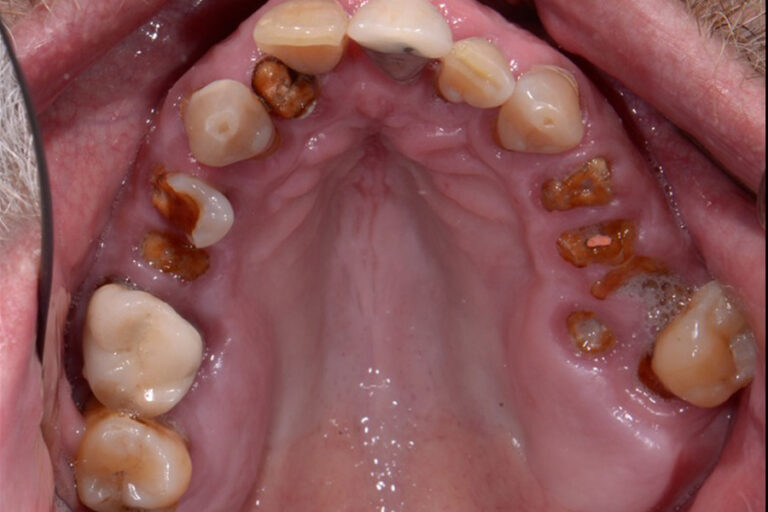

Dentures are removable prosthetic devices designed to replace missing teeth and restore function and aesthetics. They can be full (for an entire arch) or partial (for multiple missing teeth).

- Full (complete) dentures – Replace all teeth in an arch.

- Partial dentures – These fill in gaps when some natural teeth remain.

- Immediate dentures – These are Placed right after tooth extraction for immediate function.

The process typically takes several weeks and includes impressions, fittings, and adjustments. Immediate dentures are available the same day but may need refinements as the gums heal.